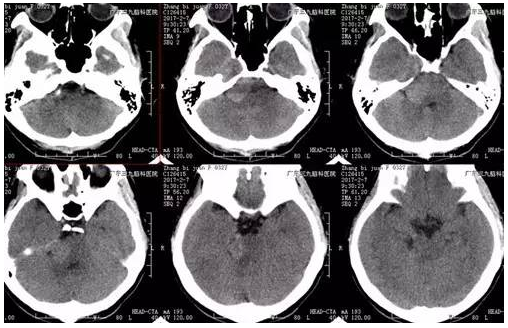

张女士,32岁,因右侧面部针刺样痛疼伴麻木持续2月余未有缓解,速来医院就诊,门诊CT提示右侧中后颅窝等密度影,收入住院治疗。入院后完善相关术前检查,术前DWI检查示右侧跨中后颅窝占位性病变呈低信号,术前磁共振示哑铃状病变,各序列以高信号为主高低混杂信号影,瘤体约4.5cm×3.7cm×3.3cm,完善检查后,行右侧中后颅窝占位性病变切除术,手术由神经一科主任张良主刀完成。术程顺利,术后患者恢复良好,未见并发症,术后MR提示肿瘤切除。